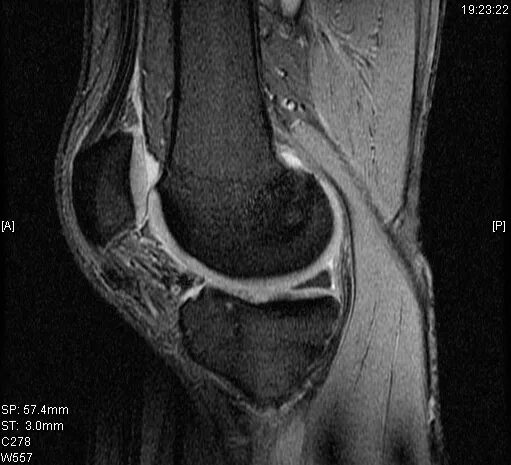

Мрт суставов химки